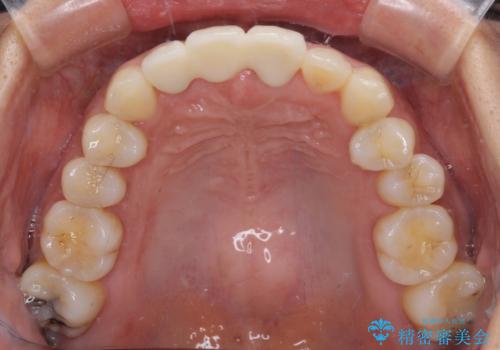

抜歯後は歯肉が痩せてしまうため、歯肉移植を行って歯肉の形態を改善した後、オールセラミックブリッジにて補綴することとしました。

歯肉移植により歯肉ラインや歯の形態を整えることができ、ブリッジによる補綴としたことで舞えば全体の色調を整えることができました。